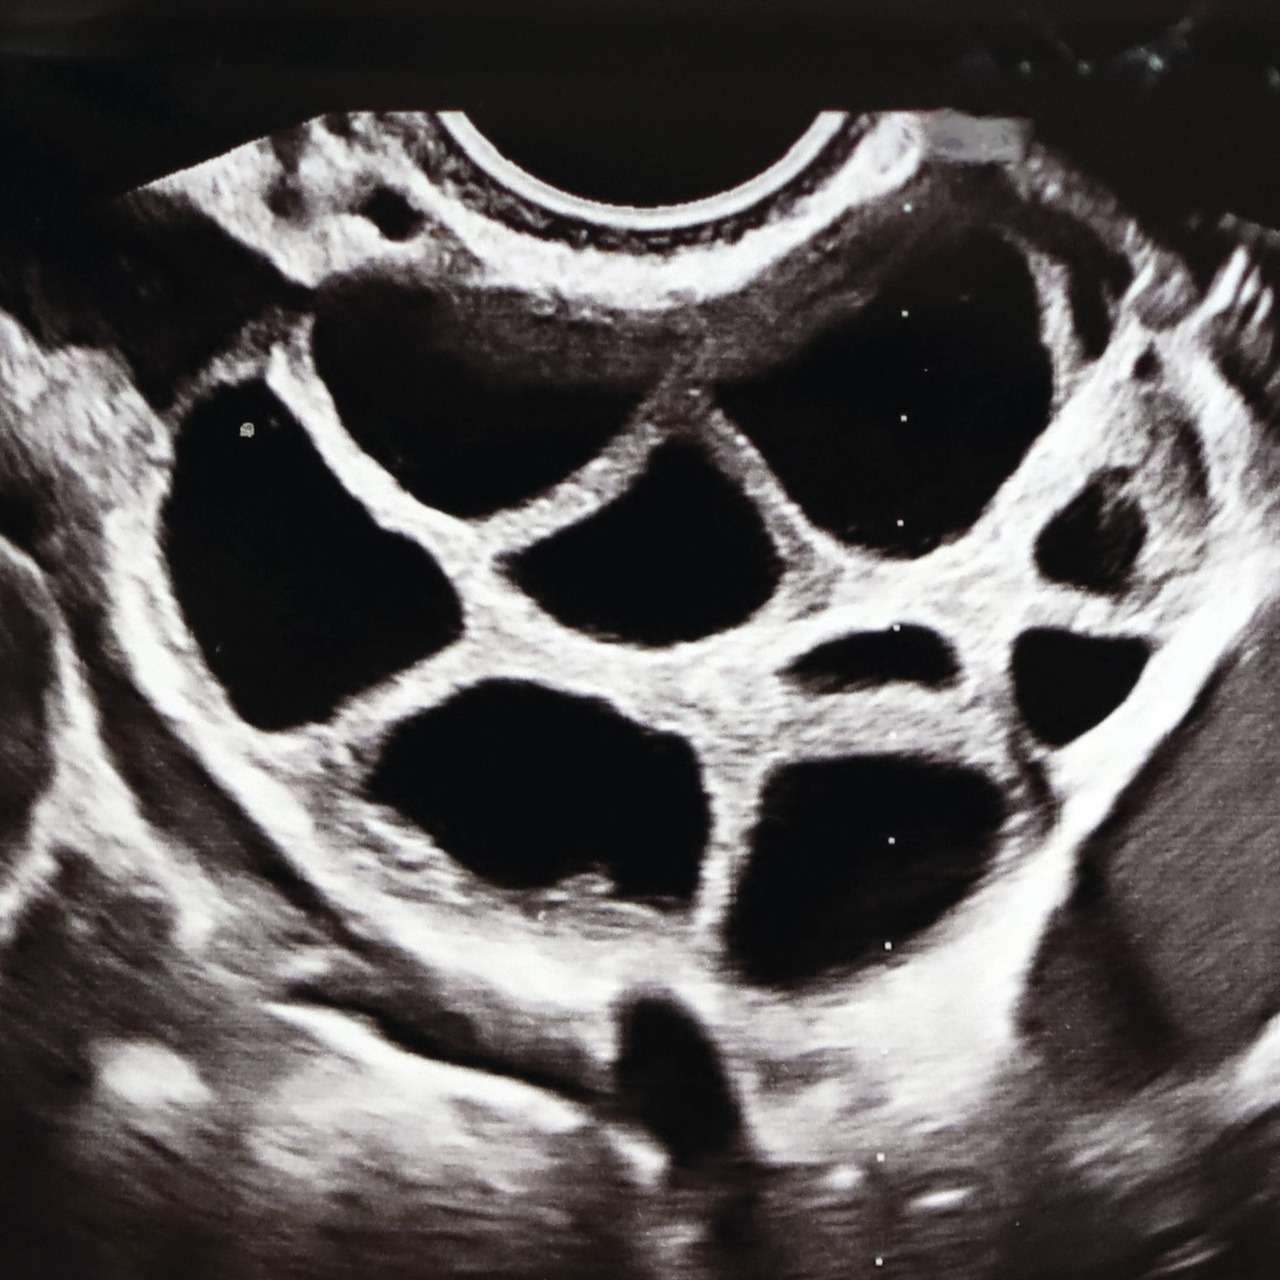

Elles se font au laboratoire, dans des conditions d’asepsie et en atmosphère contrôlée (température, pH, CO2). Le jour de la ponction (J0), les liquides folliculaires sont transportés au laboratoire le plus rapidement possible, et les complexes cumulo-ovocytaires (CCO) [fig. 3] y sont recherchés sous loupe binoculaire et mis à incuber dans un milieu de culture approprié.

Chaque complexe cumulo-ovocytaire est mis en présence d’un peu moins de 100 000 spermatozoïdes mobiles préparés. La fécondation s’effectue dans des incubateurs adaptés (incubateurs classiques ou de paillasse) [fig. 4].